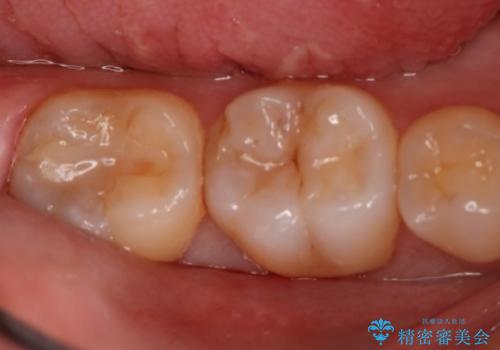

- 右下6・7番の虫歯治療を主訴に来院された患者様です。

精度が高く見た目が良いものを希望されたので、切削量・形態を考慮しセラミックインレーでの治療を計画しました。